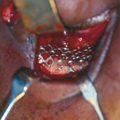

Isolated orbital floor fractures (blowouts) are often the result of impact injury to the globe resulting in a sudden increase in intraorbital hydraulic pressure. This kinetic energy is transmitted in an inferior and medial vector to the orbital floor (hydraulic theory) (Figure 13.1). Alternatively, the posterior transmission of a direct blow to the infraorbital rim causes buckling and resultant fracture of the orbital floor (buckling theory) (Figure 13.2). Fractures of the orbital floor can increase the volume of the orbit with resultant enophthalmos and hypoglobus. These can be highlighted on preoperative (Figure 13.3a–c) and postoperative (Figure 13.4a–c) computed tomographic (CT) scan imaging. In addition, the inferior rectus or periorbital soft tissue can become entrapped within the fracture line, resulting in restriction of extraocular eye movements. Table 13.1 indicates the special equipment used to surgically manage this injury.

A marking pen is used to make a surgical markings 2 mm inferior to the lower border of the tarsal plate (Figure 13.5).

The medial extent of the markings should be in line with the inferior punctum.

The lateral extent of the markings should be several millimeters medial to the lateral canthus.